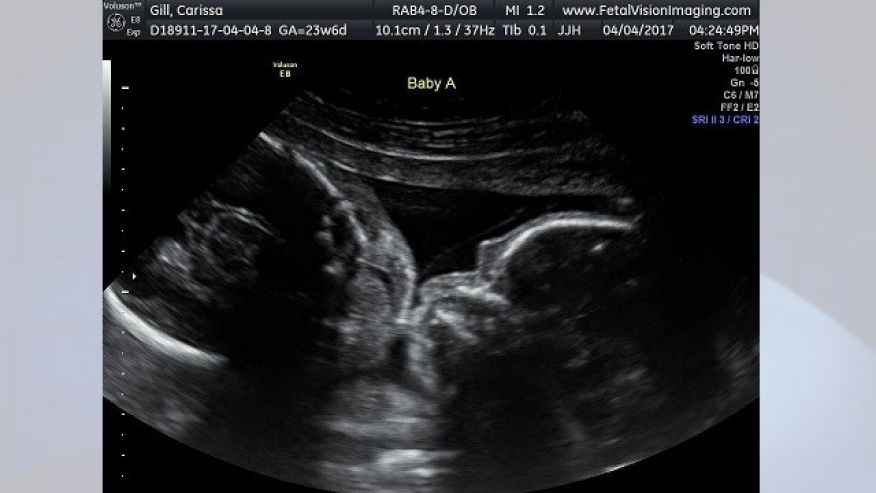

Carissa Gill, sinh sống tại Croydon (London, Anh) đang mang thai cặp song sinh 24 tuần tuổi. Cô đến phòng khám thai Vision Imaging tại Levittown cùng bạn trai Randy. Cả hai người vô cùng bất ngờ khi hình ảnh siêu âm cho thấy hai thai nhi đang trong tư thế quay đầu vào nhau và gần như môi chạm môi.

chia sẻ hình ảnh thai nhi trong lần siêu âm gần nhất tại phòng khám thai Vision Imaging. Ảnh: Carissa Gill. |

Trước khi siêu âm, Carissa cảm giác em bé trong bụng - Isabella và Callie cử động khá mạnh trong bụng mình như thể đang rúc vào nhau. Nhưng cô không nghĩ rằng em bé lại có biểu cảm như vậy.